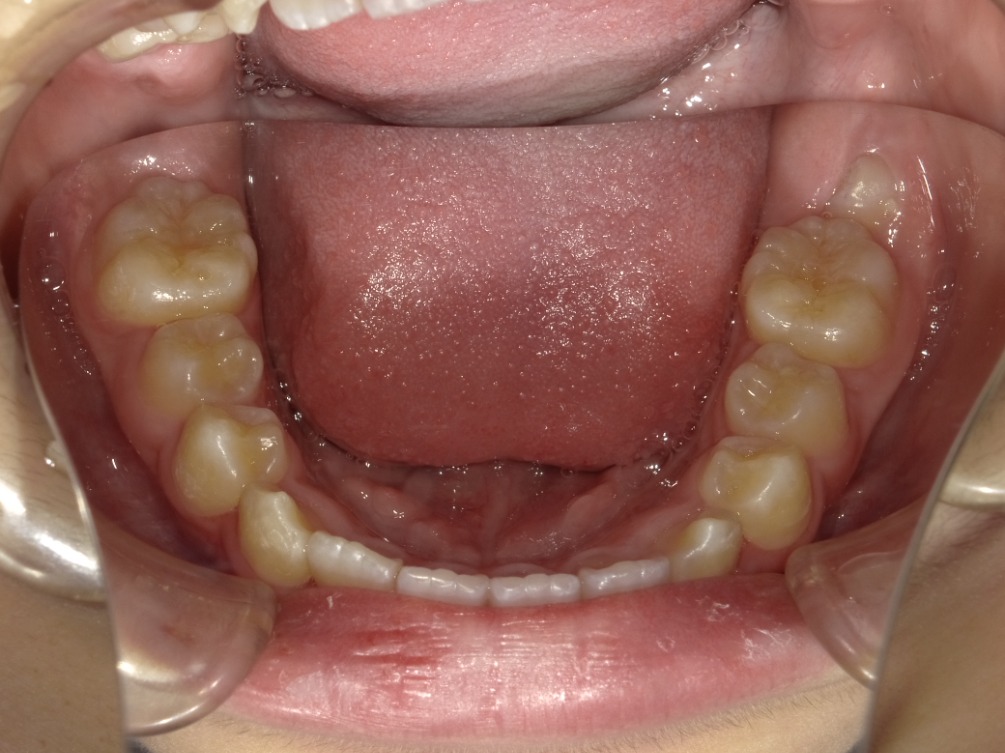

• BEFORE

症例集 インビザライン 下顎

AFTER

下顎